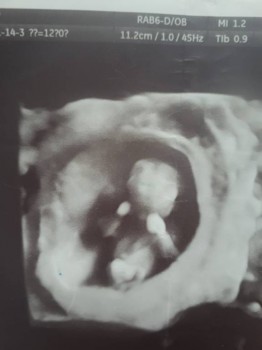

Девочки, да не примут такого никогда, сейчас от 500 г порог выхаживания,раньше от 1000 был,перинатальные центры стрят, от 24-25 недель детишек уже выхаживают.

И какие 22,там в 12 недель уже все есть и ручки и ножки.

Узи Лиза,11,2 см,чуть больше 12 недель

Голосуем ПРОТИВ петиции  - 20190322_141848.jpg